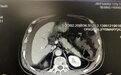

腹部增强 CT 提示:胰腺炎待排;腹盆腔积液,双侧胸腔积液;肝脏小囊肿,胆囊炎,左侧肾前筋膜增厚。

当地医院 CT 提示胰腺稍肿大,但是胰腺周围无明显渗出;今天在我院行增强 CT 提示肠管无明显扩张,胰腺周围征象未指向「重症胰腺炎」。

这个病人是胰腺炎吗?胰腺炎的诊断标准:腹痛、血淀粉酶超过正常值三倍以上、影像学支持;3 条中符合 2 条就可诊断了,这个病人是符合标准的,他甚至有暴饮暴食的诱因、肾功能损伤、血钙降低等表现,可是这个胰腺形态的确不像。